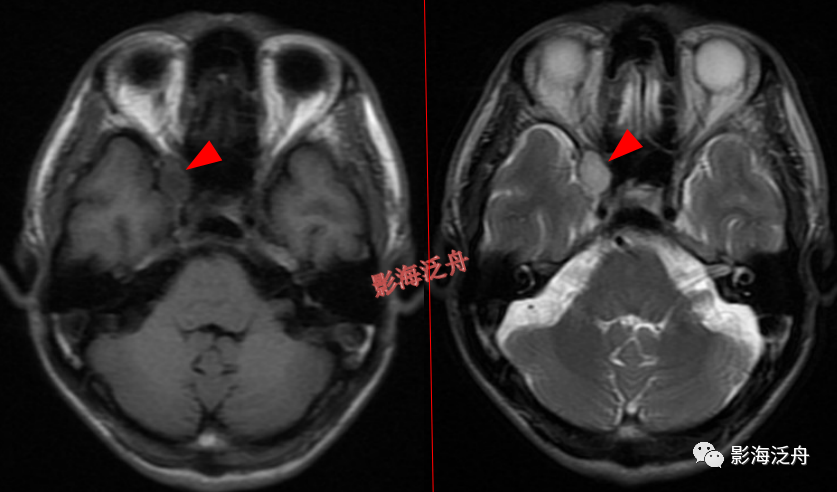

右侧侧脑室体部囊性占位(红箭),整体信号与脑脊液一致,病灶边缘部分显示,透明隔稍移位。

灰质移位,患者既往有癫痫病史。右侧侧脑室前角及左侧侧脑室后角可见异位的灰质结节(红箭),与大脑皮层下的灰质信号一致(绿箭),灰质异位患者多伴有癫痫症状。

透明隔缺如,我自己漏诊过的病例。上面有很多正常的图像可供对比观察。